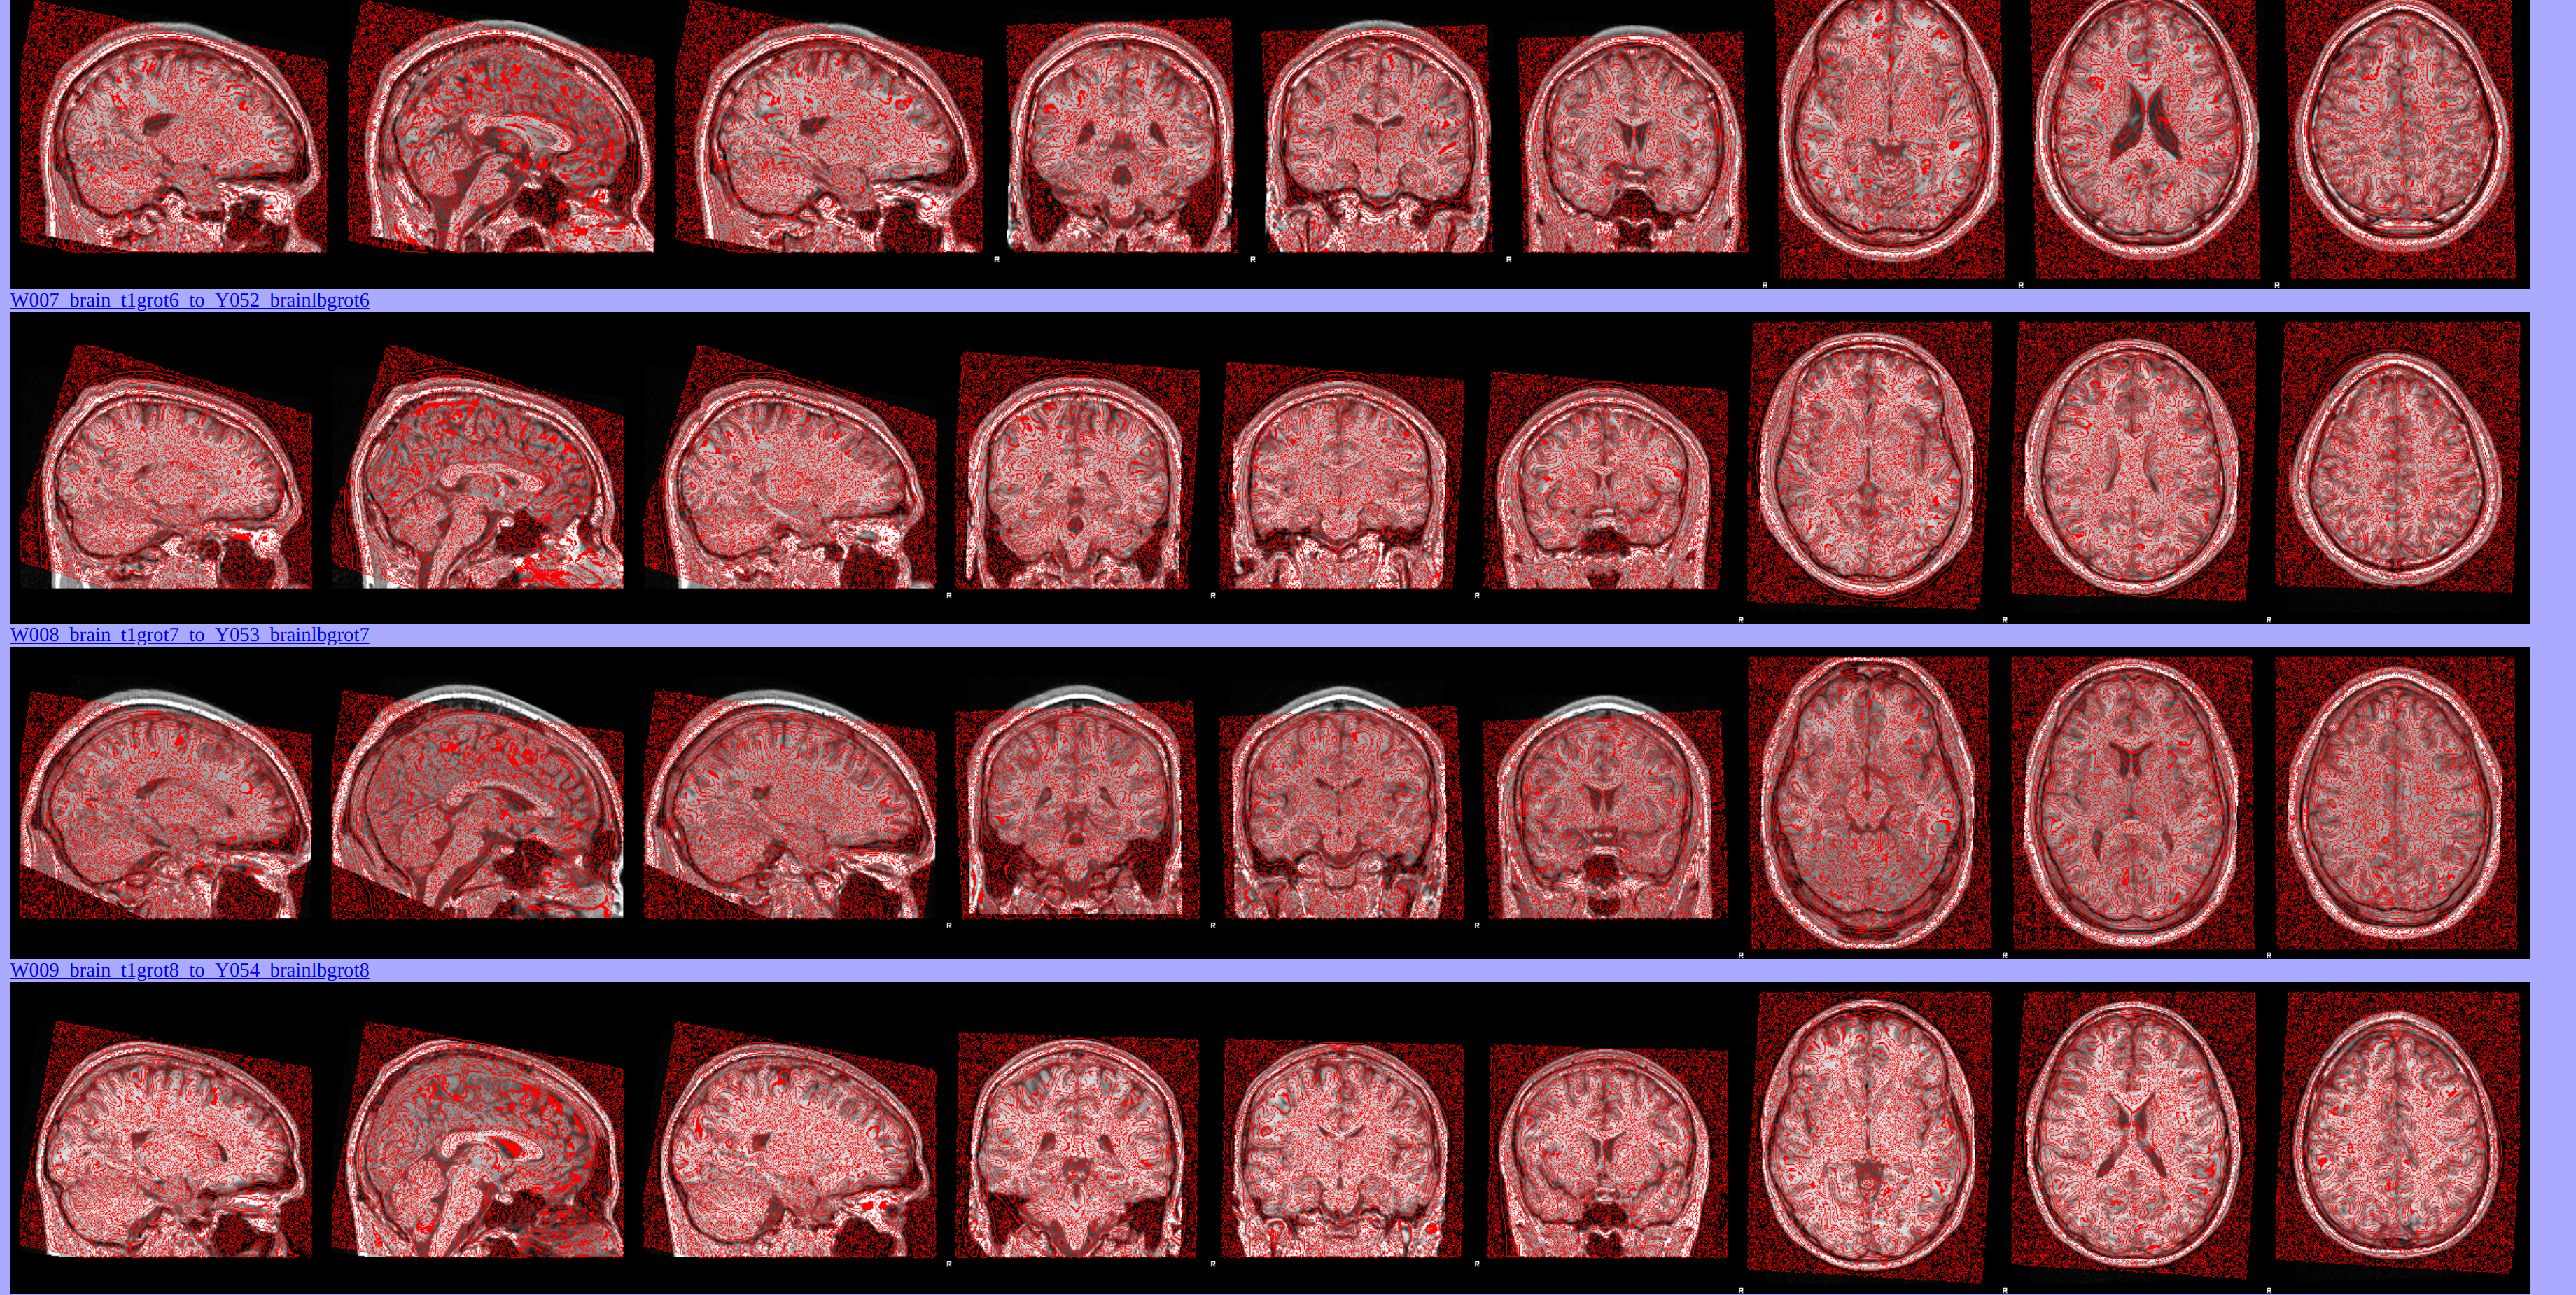

MRI data have been preprocessed using FSL tools.

Voxel-Based Morphometry (VBM) Analysis

Grey matter volume differences between athletes and non-athletes have been investigated using FSLVBM [FMRIB’s Software Library - Voxel-Based Morphometry]